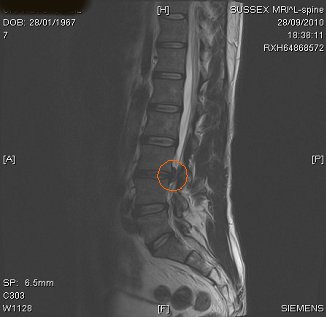

| MRI scan confirms large disc prolapse |

Finally, an MRI scan revealed that Neil was suffering with a prolapsed disc. Steve Morris decided to treat Neil with a programme of IDD Therapy. Neil gained relief within days of treatment.